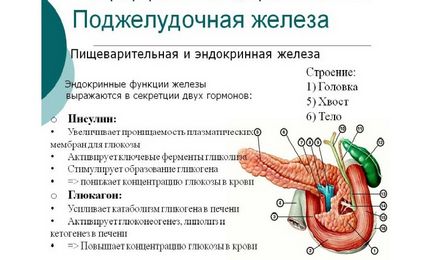

Az emberi hasnyálmirigy hormon termel mintegy 10, a legjelentősebb, amely az inzulin, a glukagon és szomatosztatin. Hormonok a hasnyálmirigy felelős energia-anyagcsere a szervezetben. Szabályozzák az emésztési folyamatot, és aktívan részt venni benne. Túlkínálat vagy inzulinhiány és a többi összetevő vezet romlása az emberi állapot.

Az összehangolt működését az egész emésztőrendszer nem lehetséges anélkül, hogy a hormonális által végrehajtott hasnyálmirigy. Ez a szerv termeli három fő hormonok:

Mindegyik faj által szintetizált bizonyos sejtek. A glukagon felelős alfa-sejtjeinek az inzulin - a béta-sejtek, és a generációs szomatosztatin részt delta-sejtek. A szerkezet a endokrin sejtek a hasnyálmirigy szekretálnak lehetővé teszik kívánt anyagokat közvetlenül a hajók.

Minden hormonnak megvan a maga szerepe és funkcionális, ami lehetővé teszi, hogy aktívan részt vegyenek az emésztés során, és szabályozzák a működését, a gyomor-bél traktus.

A fő funkciója az inzulin

Készítmény fő hasnyálmirigyhormon végezzük egy automatikus szinten. Inzulin, amely részt vesz a rendelkezés a sejten belüli energia hatással van minden sejt a szervezetben. Vezető az a feladata, hogy normalizálja a vércukorszintet - nevezetesen a dia.

Ezt a folyamatot befolyásolja számos mechanizmus. Ezek közé tartoznak:

- fokozott permeabilitása sejtmembránok;

- glikolízist (glükóz oxidáció);

- növekedése a cukor készleteket;

- gátlást anyagok, a végén folyamat, amely az, hogy a glükóz.

sejtpermeabilitás által elért specifikus receptorok aktiválásán lokalizált a sejtmembránban. Glükózfelvétel sejtbe akkor jelentkezik, amikor a számot képviselt receptor. A glikolízis a májsejtekben vezetett enzimek. Az aktiválás az inzulinrezisztencia miatt. Való hasítás után a vércukorszint csökken hatása alatt ezen enzimek.

Fokozott cukor tartalékok belül végrehajtott májsejtek és az izomszövet. A folyamat aktiválja az enzimek a glükóz-6-foszfátot. Gátlása anyagok, melynek végső célja a fejlesztési glükóz a májban sejtek további hormonok. Ezek közvetlenül részt vesz a szintézis a vércukorszint.

Az inzulin csökkenti a vér glükóz koncentrációt.

A szerepe a glukagon és szomatosztatin

Ez a hormon az ellenkező hatást: ez, mint az inzulin, figyeli a vércukorszint, de amikor a cukor mennyiségét gyorsan csökken, a hormon gyorsan átalakul, és kompenzálja a hiányosságot. Ezen túlmenően, a glukagon felelős a elnyomása gyomorsav-szekréciót.

Normalizálása glukagon rögzítve közvetlenül étkezés után. A szintézist eljárást végzik köszönhetően ez a hormon alfa-sejtek. Egyéb alkatrészek, az emésztőrendszer gyakran vesznek részt benne.

A glukagon az alábbi funkciókat.

- Aktív hasítás glikogén lokalizálódik a májban és az izmokban.

- Komponensek szétválasztásának lipid, amely szabályozza a zsír lebontását.

- A glükóz képződést a nem szénhidrát anyagok típusú.

Szomatosztatin gátolja a szintézis más hormonok. Ez az egyedülálló tulajdonság azzal gyulladásos léziók a hasnyálmirigy. A szomatosztatin aktivitása felelős csökkentő glukagon rendezett kiürítését a gyomortartalom és a lassuló termelés gasztrin. Továbbá, ez biztosítja a folyamat fokozatos cukor felszívódását élelmiszerek és csökkenti a vér áramlását a hasüregben. Készítmény az anyag végzik nemcsak a hipotalamusz, hanem a sejtek az emésztőrendszer és az idegrendszer.

A glukagon aktívan részt vesznek a folyamatban, növeli a glükóz szintje a vérben. A szomatosztatin leállításáért felelős más hormonok termelésére a hasnyálmirigy.